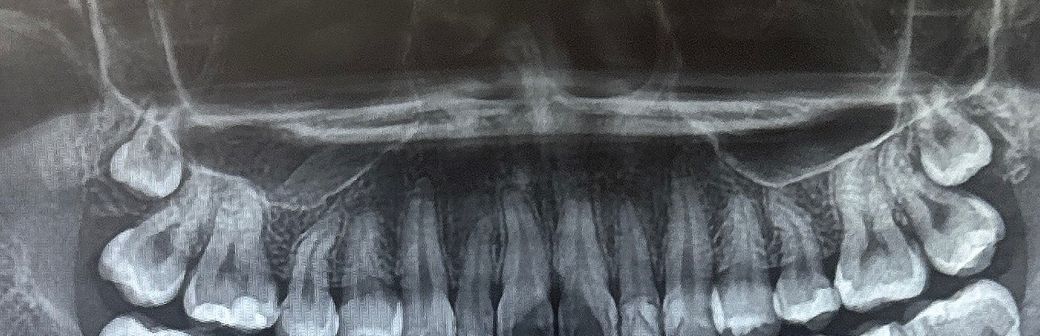

상악 사랑니 발치 난이도 어떤가요?? (사진O)

상악 사랑니 두개 각각 난이도 어떤가 궁금합니다

사랑니가 많이 깊은 편이기 때문에 난이도 자체는 높은 편입니다. 전문의 선생님이면 괜찮을겁니다.

상악의 경우는 발치 자체는 어렵지 않지만, 시야 확보가 좋지 않아 보이고 치아 아래쪽에 잇어서 난이도가 높아 보입니다.

상악에 있는 사랑니가 매우 깊게 매복되어 있으며 난이도는 높은 곳으로 생각됩니다. 사랑니가 완전히 매혹되어 있고 문제를 발생시키지 않으면 발치를 할 필요는 없습니다.

자세한 확인을 위해서 치과에서 진료를 받아보는 것을 권유드립니다.

잇몸뼈에 완전히 매복되어 있습니다. 반드시 빼야하거나 그런 상황은 아니지만 추후 물혹을 형성할 수도 있기 때문에 예방적으로 빼주는 것도 나쁘지 않습니다. 외과 전문의라면 믿고 맡기세요. 외과 전문의 입장에서는 높은 난이도 아닐 겁니다.